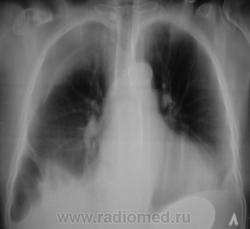

правосторонний пневмоторакс. Синус справа не определяется,что может говорить о плевральном выпоте, причём давнишнем. Н\доля ателектазирована, возможно за счёт непроходимости бронха. Срединная тень смещена немного влево. У меня напрашиваются два диагноза: ТВС или онкол. процесс. Может быть ещё последствие травмы.

Правоторонний пневмоторакс. А бок?

Правосторонний пневматоракс сохраняется, осумкованные полости с жидкостью. Слева тоже жидкость обьявилась. Какой-нибудь сопутствующей патологии у женщины нет?

ИМХО:  Эмиема плевры с 2-х сторон, осложнённая пневматораксом справа.. Ателектаза нижней доли справа не должно быть, т.к. сосуды лёгкого имеют обычное расположение ( на месте, что нехарактерно для ателектаза). Все это должно быть связано с клинико-лабораторными данными.